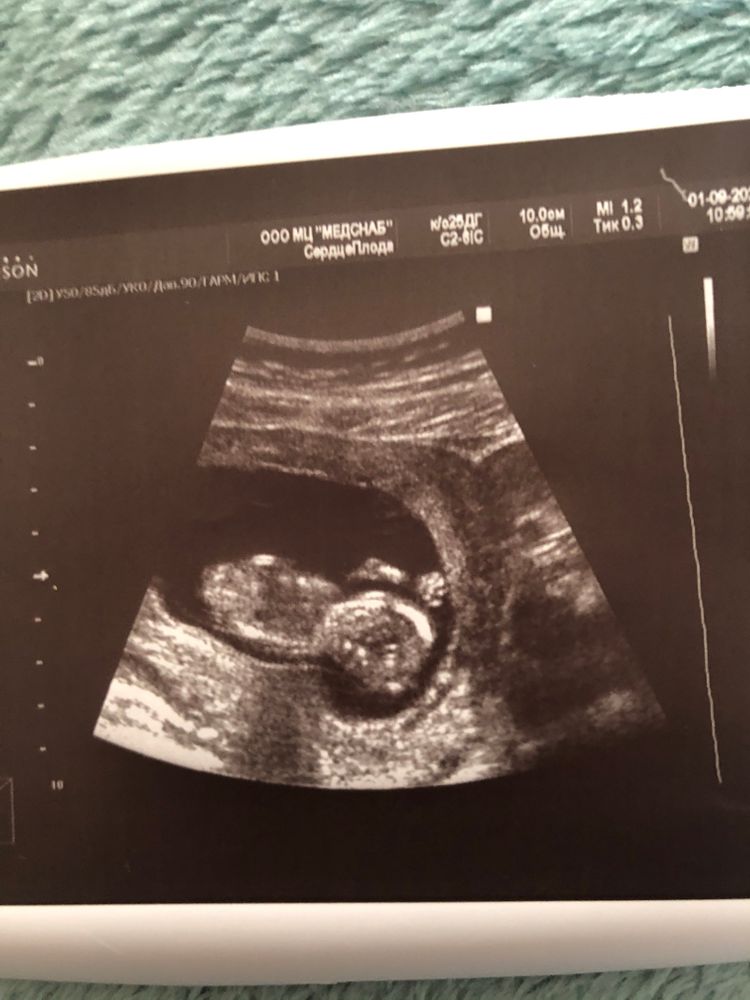

Результаты: УЗИ, КТГ, доплера, скринингаДевочка, привет! Пришла с первого скрининга, вроде все хорошо, только вот мне сказали о краевом предлежании плаценты, опасно это?

Ну и по традиции опытные девочки, предположите кто в животике?) доктор сказал даст ответ только на 2 скрининге😒

Про плаценту рано говорить, она чаще всего поднимается и никаких проблем не создаёт. А насчёт пола, у вас фото с неудачного раскурса, к сожалению здесь не видно то самое место😁